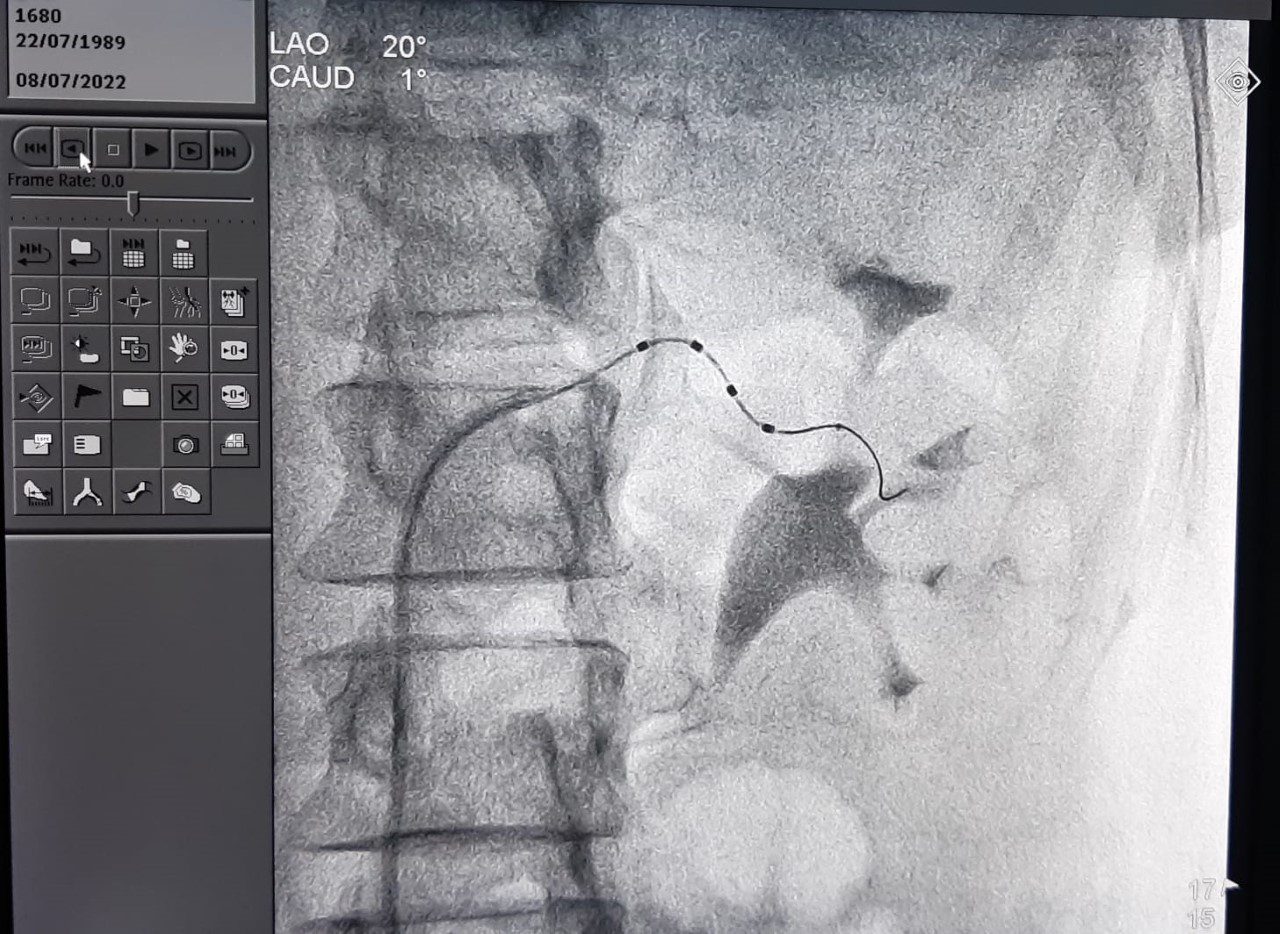

A vida da jovem Graziele Góis ganhou um novo capítulo na noite de sexta-feira (8), quando foi submetida à técnica de denervação renal, um procedimento inédito na Bahia. Antes, ela fazia uso diário de 29 comprimidos em dosagem máxima, cansava muito, tinha limitação de esforço e dificuldade para dormir.

Antes da denervação renal, via cateter, os profissionais que acompanhavam a paciente tentaram o controle da pressão arterial com a prescrição de remédios. Aplicadas as primeiras doses sem resultado, foram aumentando a qualidade de medicamentos, mas seguiram sem a resposta desejada. Por isso, indicaram a denervação renal, método invasivo usado para o tratamento de hipertensão.

No início da noite da sexta-feira passada, uma equipe, comandada pelos cardiologistas intervencionistas Gláucio Werneck e Rodolfo Staico, realizou o procedimento de denervação renal, concluída em duas horas. Graziele Góis recebeu alta médica nesta segunda-feira (11), com pressão de 12X8. Esse quadro se manteve nesta terça.

Chefe do Serviço de Hemodinâmica da Santa Casa de Itabuna, o médico Gláucio Werneck destaca o pioneirismo do uso da técnica da denervação renal no sul da Bahia. “Estamos atentos sempre às novas tecnologias surgidas e melhores técnicas para o controle e tratamento de doenças cardiovasculares graves”, explica.